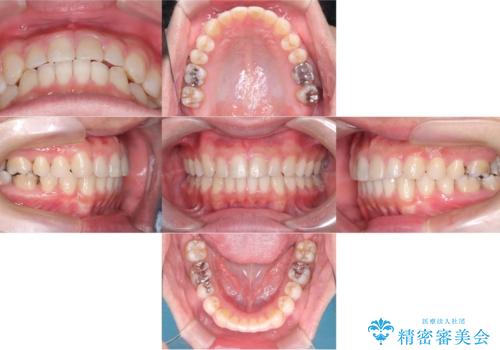

- 前歯の隙間と歯のデコボコを主訴にご来院された患者様です。

加えて、上下の奥歯が全く咬み合わないシザーズバイトの状態も認められました。

矯正検査の結果、非抜歯でインビザラインによる治療が可能と判断し、治療を行いました。

歯の隙間とデコボコ、シザーズバイトも改善され、咬み合わせや見た目が整い、患者様にも大変ご満足いただけました。